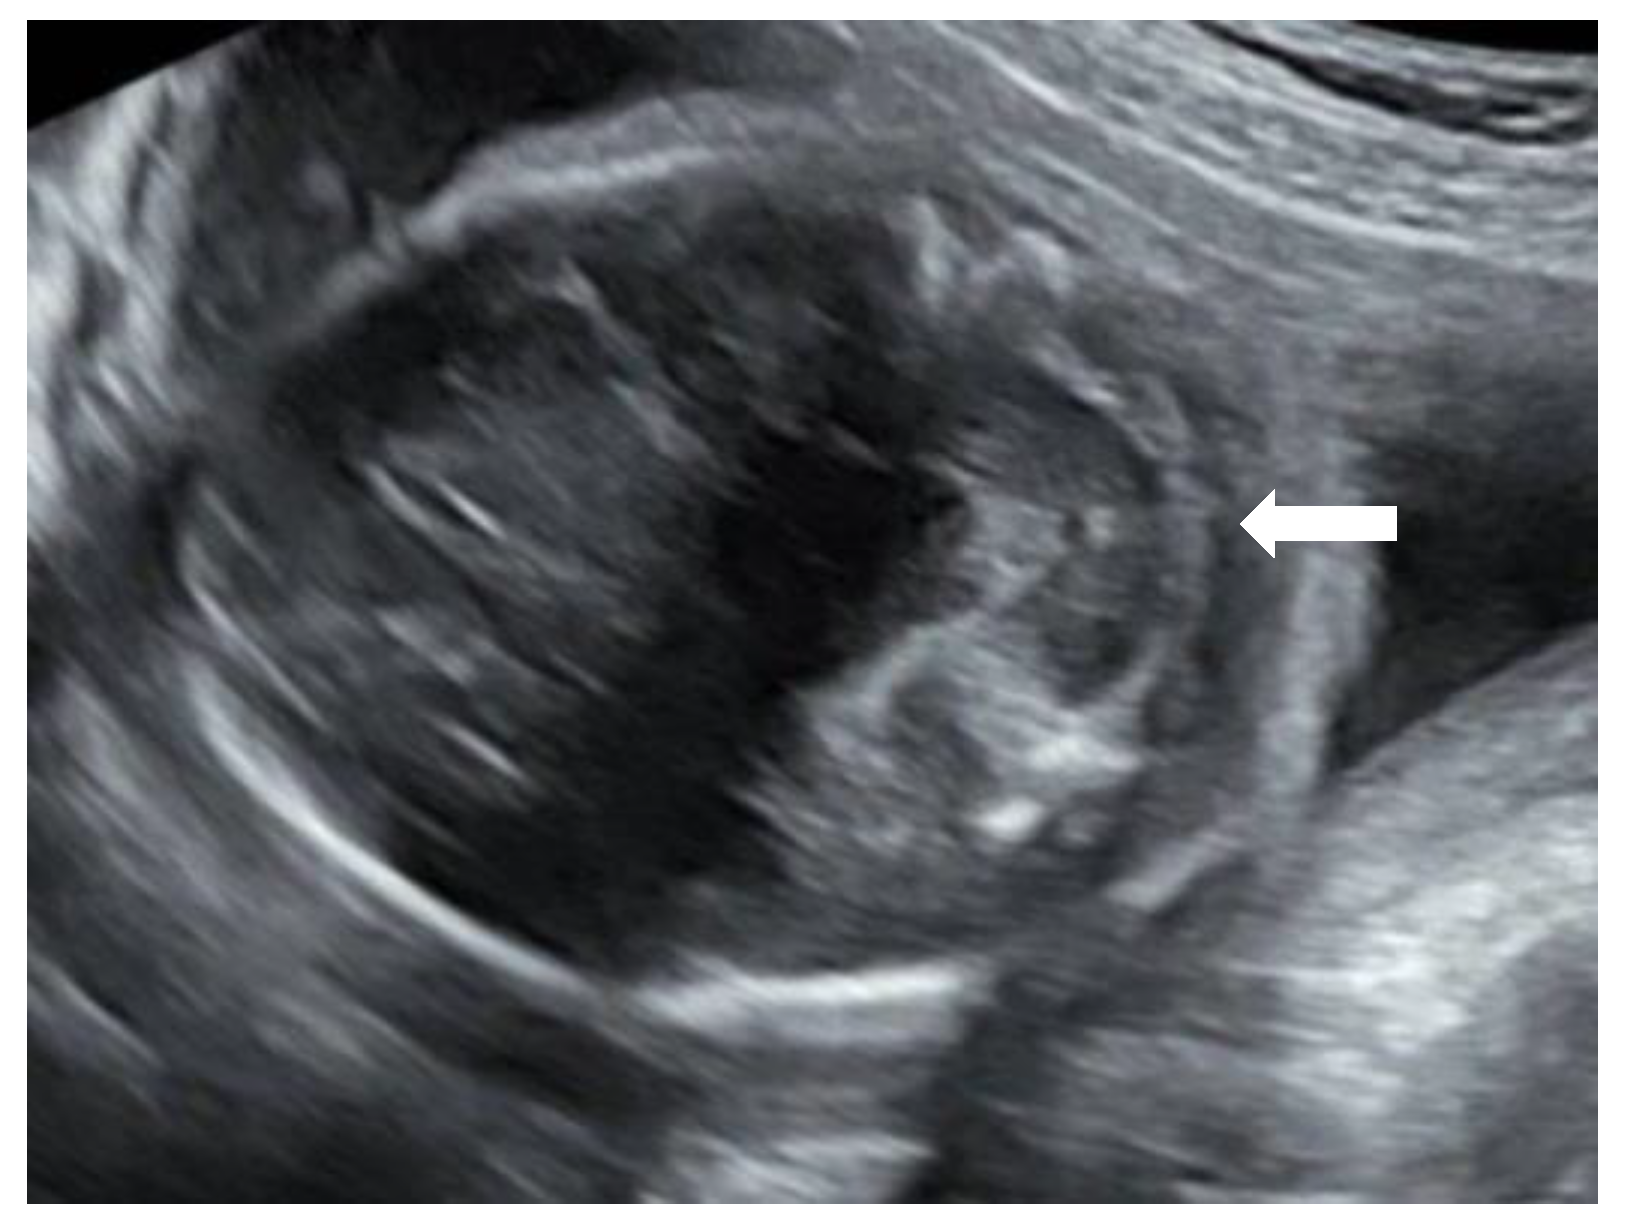

A 27-year-old primigravida was referred to the outpatient clinic of our hospital at a gestational age (GA) of 17 + 3 weeks following detection of a fetal unilateral hydronephrosis by the peripheral gynecologist. Ultrasonography demonstrated a duplex collecting system in the left kidney with hydronephrosis of the cranial pole, moderate dilatation of the upper pole ureter, and mild dilatation of the lower pole ureter. The cerebellum at that time showed a minimal posterior curving (

Figure 1), but no distinct banana-sign. Inspection of the spine was inconspicuous. The patient was reevaluated in our center at 24 weeks GA. The hydronephrosis of the upper pole of the left kidney remained stable. However, the cerebellum presented a banana-shape with herniation of the hindbrain onto C2 and minimal lemon-sign of the skull (